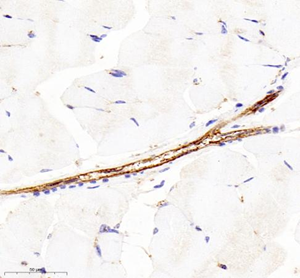

| Immunohistochemistry of paraffin embedded mouse Skeletal muscle using CD31 (GB11063-3) at dilution of 1:400 (400x lens) |